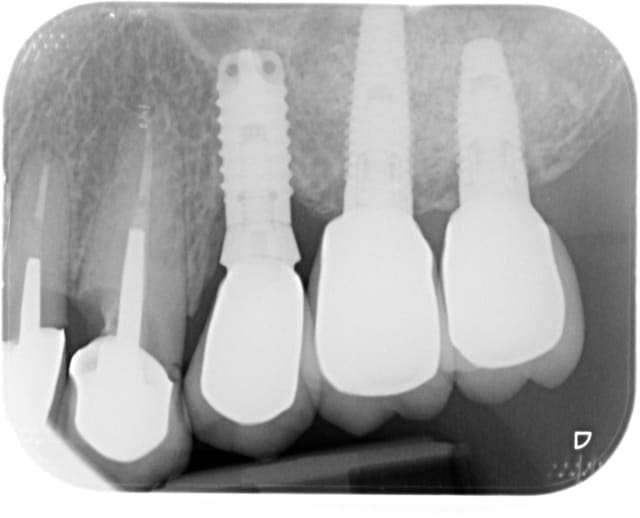

c'est celui en 24 que je n'ai pas réussi à identifier.

la couronne est mobile,ce n'est pas le premier dévissage,

couronne scellée.

hypothèse tbr?

TBR OCT-IN OU CLASSIC

TBR sans aucun doute...

et toujour une cratérisation chez TBR